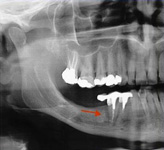

Onemocnění parodontu patří ke druhému nejčastějšímu onemocnění v dutině ústní, ihned po zubním kazu. Nejčastějším problémem je gingivitis- zánět dásní a také parodontitis - zánětlivé onemocnění postihující závěsný aparát zubů, přilehlou dáseň i kost. Mezi časné projevy gingivitidy patří krvácení dásní, které může v případě parodontitidy přejít ve tvorbu parodontálních chobotů, spojené se zápachem z úst, tvorbou hnisu, bolestmi a viklavostí zubů v důsledku ztráty kosti. Tomuto onemocnění se dá úspěšně předcházet pravidelnými kontrolami, sanací chrupu a péčí v rámci dentální hygieny.

Periometr - první plně automatizovaný přístroj pro zjištění periodontálního statusu pacienta - diagnózy, léčby a profylaxe parodontitidy a dalších onemocnění. Díky správnému určení periodontálnímu statusu pacienta lze včas odhalit a minimalizovat objevující se obtíže.

Používá se i v implantologii, při stanovení diagnózy a léčby periimplantitidy (zánětu měkkých tkání a kosti v okolí implantátu).